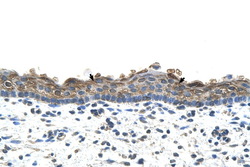

Immunohistochemistry

LS-C40441 IHC